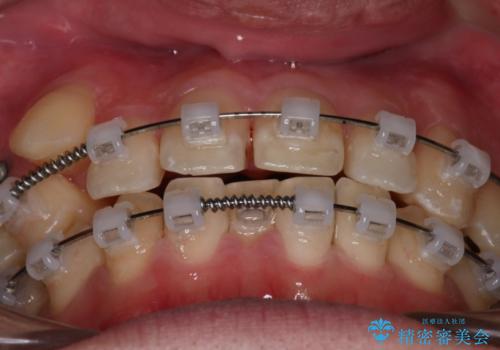

歯の移動にオープンコイルとMI(歯肉に埋入するネジ)を用いました。

非抜歯矯正だったこともあり、1年半以内という短い期間で矯正を終了することができました。